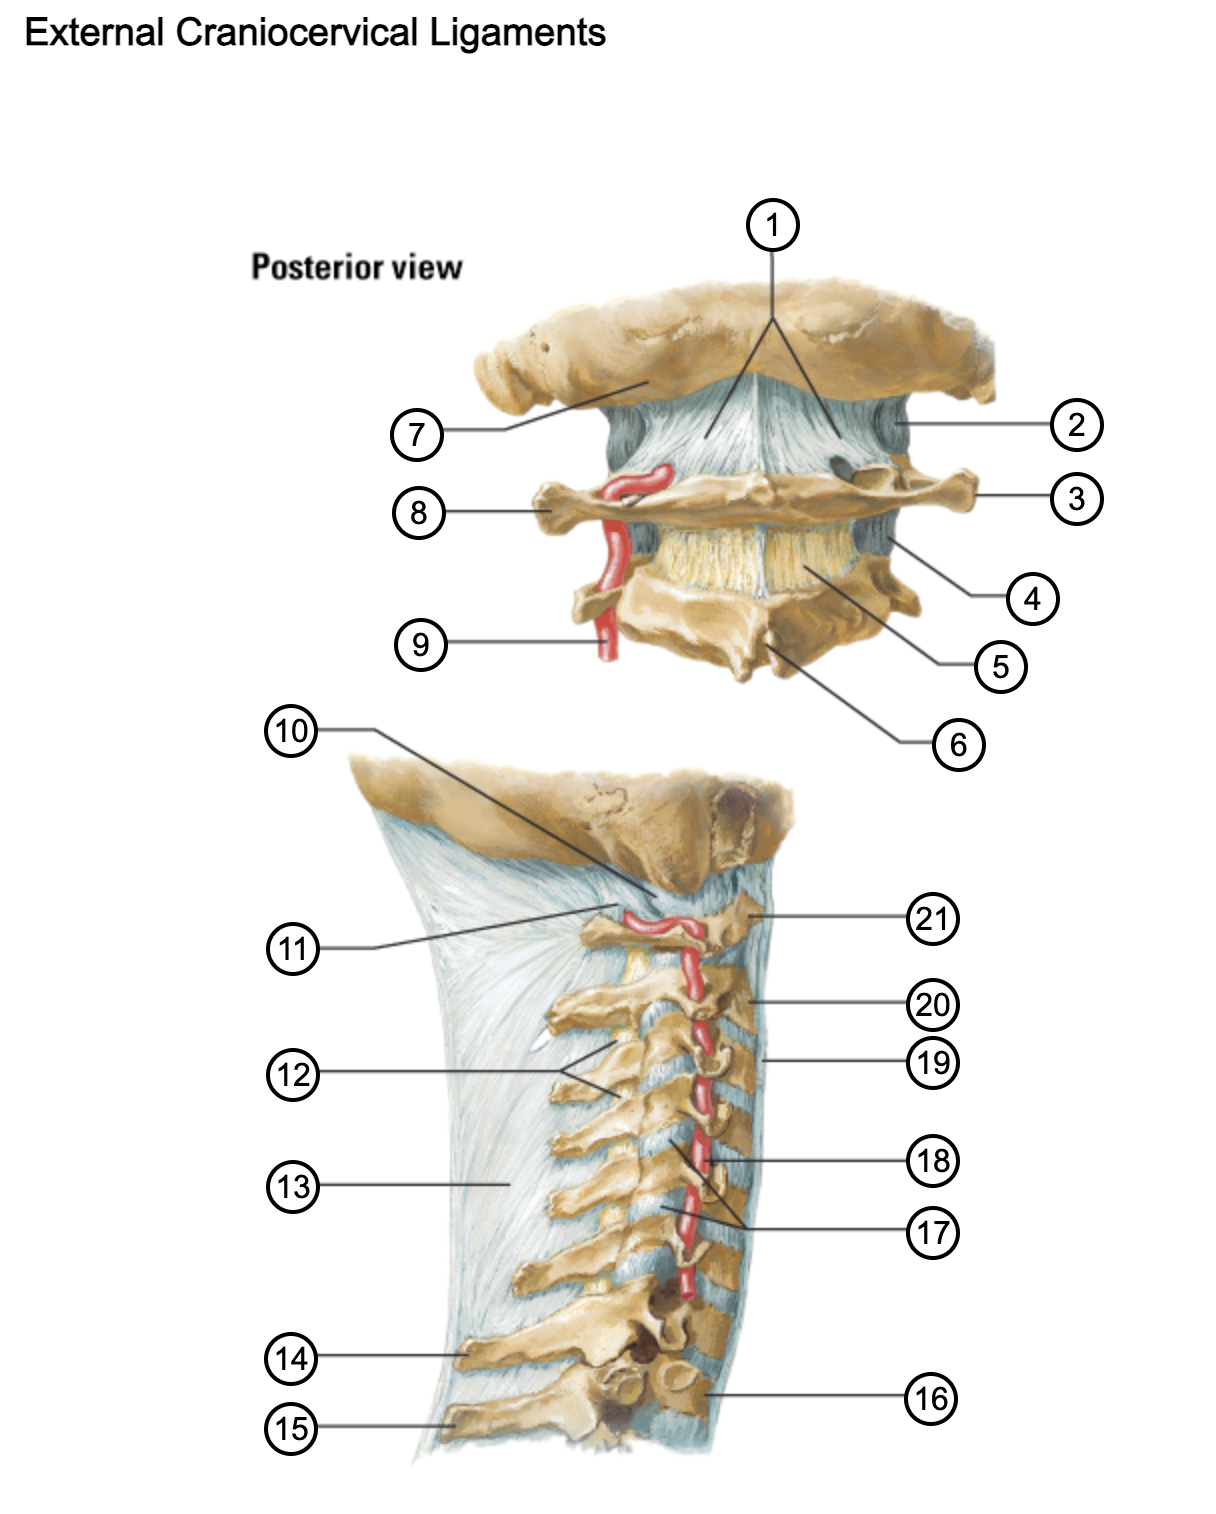

1

posterior antlantooccipital membrane

2

capsule of atlantooccipital joint

3

transverse process of atlas (C1)

4

capsule of lateral atlantoaxial joint

5

ligamenta flava

6

spinous process

7

occipital bone

8

transverse process of atlas (C1)

9

vertebral artery

10

capsule of atlantooccipital membrane

11

posterior atlantooccipital membrane

12

ligamenta flava

13

nuchal ligament

14

spinous process of C7 vertebra

15

spinous process of T1 vertebra

16

T1 vertebra

17

zygapophysical joints (C4-5 and C5-6)

18

vertebral artery

19

anterior longitudinal ligament

20

body of axis

21

Atlas (C1)